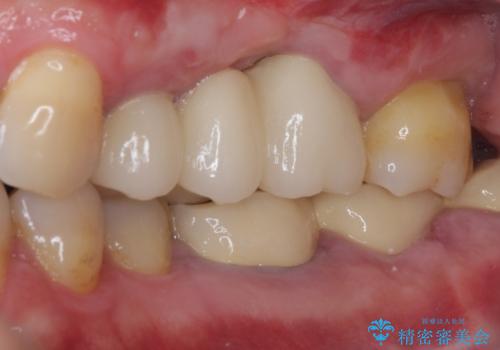

ものが挟まって痛む 割れてしまった歯のオールセラミックブリッジ治療

抜歯後、骨吸収量が多く、歯肉のラインが不揃いとなっているため骨造成術を、硬い歯肉が失われて清掃性が低下するため角化歯肉の移植術を行い、また並行して支台歯の根管治療を行っていき、環境を整えた上でオールセラミックブリッジにて補綴治療を行うこととしました。

インプラントによる補綴治療も検討しましたが、骨吸収量が多いこと、後方の支台歯が今後抜歯となる可能性が否定できないことを鑑み、将来抜歯となった際にインプラント2本を埋入することで患者様と事前にお話をしました。